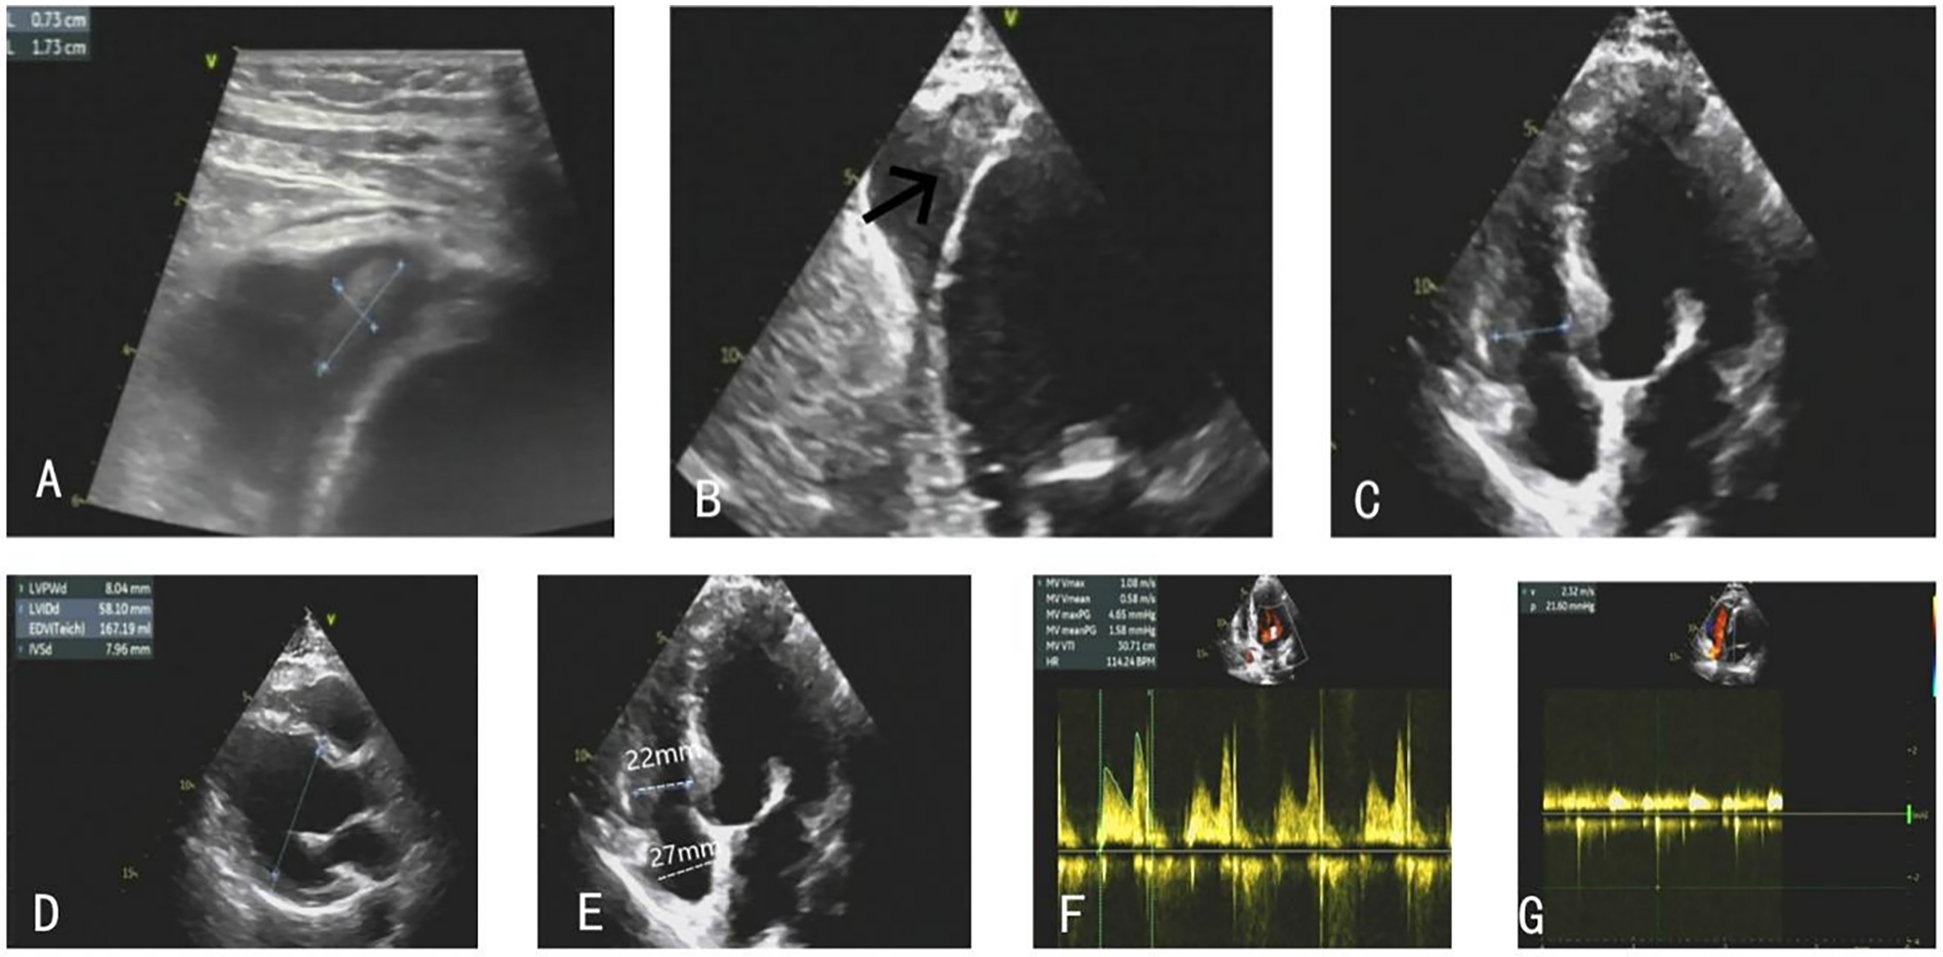

Figure 4

(A–C) The right ventricular thrombus gradually eliminated. (D–G) TTE on the follow-up showed stable clips with mild MR, and the patient's ventricular systolic function significantly improved.

At the 1-month follow-up, repeat TTE demonstrated further diminution of the thrombi. After 7 months of anticoagulation therapy, follow-up echocardiography confirmed complete resolution of the thrombus, stable clips with mild MR, and preserved valvular function. At this time, the INR was therapeutic at 2.31, with a mean mitral valve pressure gradient of 1.6 mmHg and a peak mitral inflow velocity of 108 cm/s (Figures 4D–G). No thromboembolic complications or recurrent thrombus formation were observed during the surveillance period, and noparadoxical embolic events occurred, including stroke, systemic infarction, or hypoxemia.